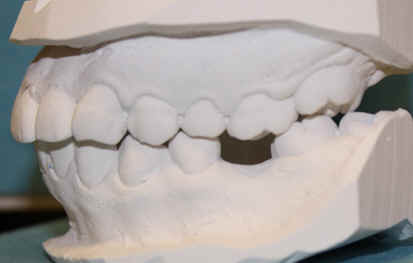

#18 mesiolingual tilt, #19 traditional implant and extract #17; once #19 implant is osteointegrated, it is to be used as an anchorage to upright #18, elastics between #15 buccal hook and 18 lingual button to correct linguoversion of #18

#14 supraeruption, mini-implants, orthodontic intrusion

Start tradtional orthodontic treatment